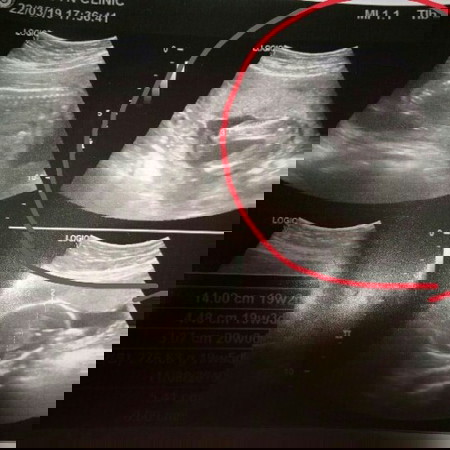

เพศทารก

แม่ๆช่วยดูหรือช่วยคอนเฟิร์มให้หน่อยค่ะว่าเพศหญิงหรือเพศชาย แม่ไม่มั่นใจ55555

ของคุณแม่น่าจะ ผญ หรือป่าวคะ ถ้าเป็นผช น่าจะมีแหลมๆออกมาแบบนี้